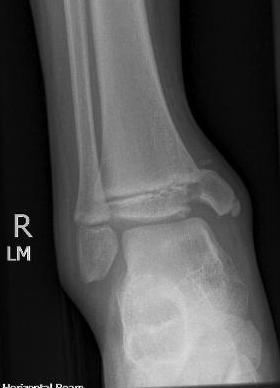

Xray

AP xray: Salter-Harris type III / Tillaux

Lateral xray: Salter-Harris Type II